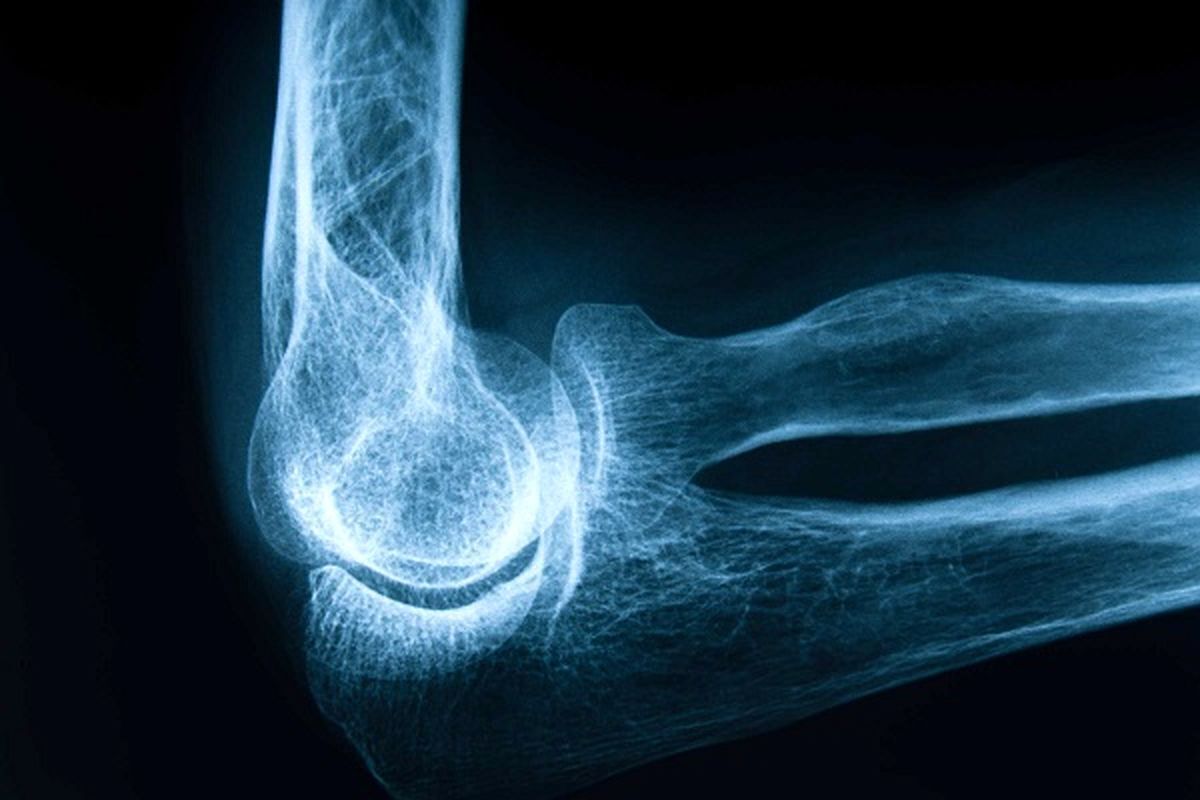

به گزارش شهرآرانیوز، از صبح که از خواب بیدار میشویم و پایمان را روی زمین میگذاریم، شاید سلامت استخوانهایمان آخرین چیزی باشد که به آن فکر میکنیم؛ همان ستونهای خاموشی که در تمام عمر بار فعالیتهایمان را به دوش میکشند، اما زمانی که پوکی استخوان مثل یک مهمان ناخوانده در وجودمان ریشه دواند و استخوانهایمان را ضعیف کرد، تازه آن وقت است که فعالیت فیزیکی حتی در حد دویدن و بلندکردن بار سنگین هم برایمان تبدیل به آرزو میشود. امروز، روز جهانی پوکی استخوان است، بیماری پنهانی که اگر امروز جدیاش نگیریم، فردا ممکن است سادهترین زمینخوردن نیز برایمان هزینهای سنگین داشته باشد.

وی میافزاید: نشانههای اولیه این بیماری اغلب خاموش و پنهان هستند؛ دردهای خفیف استخوانی، کاهش قد، قوز پشتی و شکستگیهای مکرر حتی با آسیبهای کوچک میتوانند اولین زنگ خطر باشند. متأسفانه بسیاری از بیماران ما اذعان دارند که تا بروز شکستگی جدی از بیماری خود خبر نداشتهاند و به همین دلیل، آزمونهای دورهای میتواند مهمترین ابزار برای سنجش، پایش و درمان بموقع این چالش باشد.